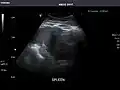

Abdominal Ultrasound (Full Exam)

STRUCTURED REPORT

(Technique: Transabdominal ultrasonography; Device: Toshiba Aplio XG)

Spleen: Normal in size.

Spleen -